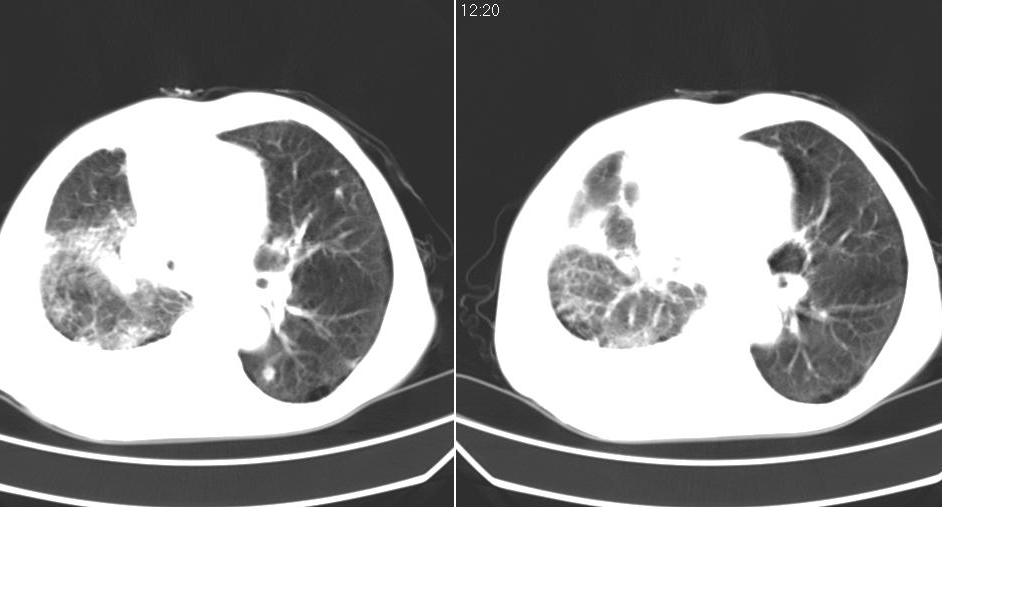

以下是引用zsl6918在2008-5-3 19:53:00的发言:[br]右肺中心型肺癌并纵隔淋巴结转移,胸膜转移,右肺癌性淋巴管炎。

以下是引用liuyue在2008-5-3 20:49:00的发言:[br]1.右侧中心型肺癌伴双肺转移瘤、纵隔淋巴结转移、右侧胸腔积液(侵及胸膜所致可能性大)。[br]2.右肺阻塞性肺炎,癌性淋巴管炎不除外。

以下是引用mzh123在2008-5-3 21:12:00的发言:[br]本人持有不同观点[br]1、右肺似有团块表现,但只有一个层面,所以本人认为还是以片为主,所以不能首先考虑肿瘤[br]2、右肺普遍成纤维化改变 并伴有片状炎症改变,和癌性淋巴管炎表现不同[br]3、所以本人认为是间质纤维化伴感染可能大 及胸腔积液